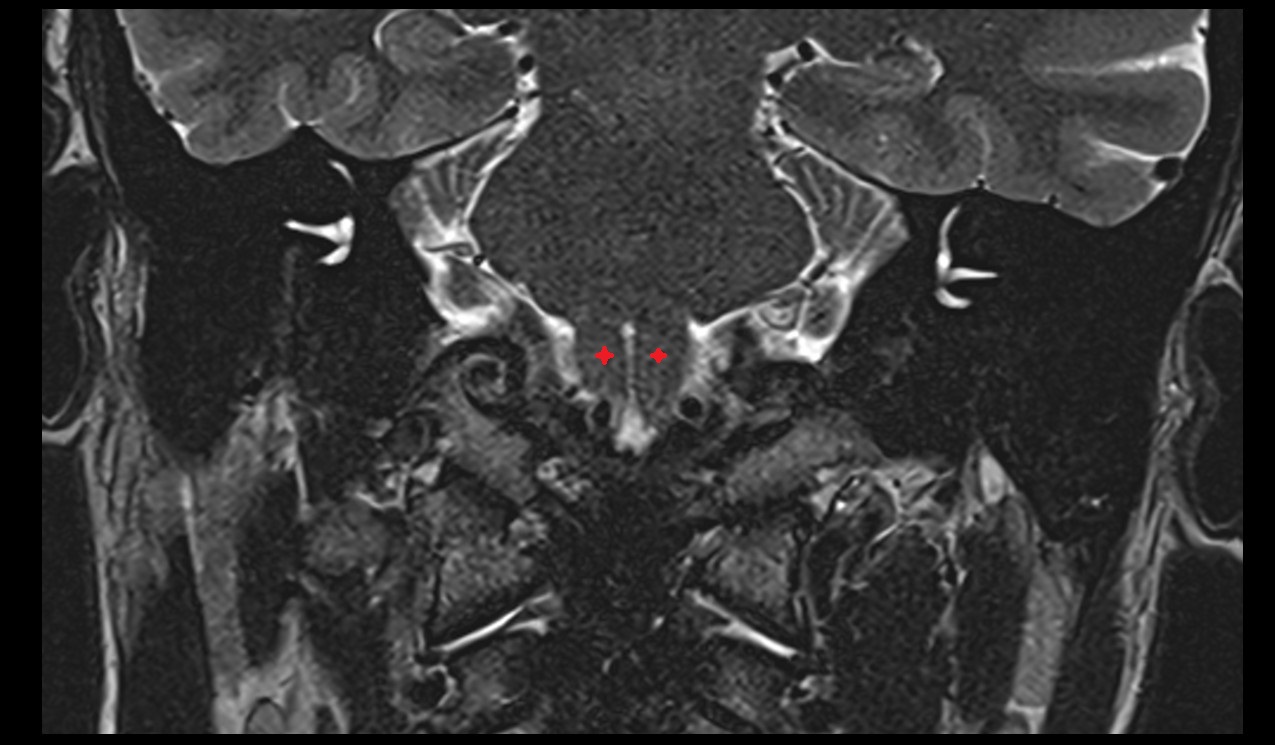

- Optic chiasm

- Optic tract